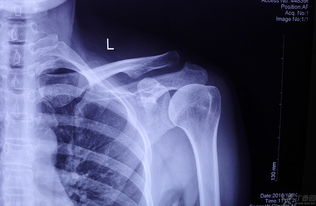

2.手術(shù)療法對肩鎖關(guān)節全脫位,即Ⅲ型損傷之病人,因其關(guān)節囊及肩鎖韌帶、喙鎖韌帶均已斷裂,使肩鎖關(guān)節完全失去穩定,上述外固定效果不滿(mǎn)意,對年齡小于45歲者,應手術(shù)修復。

常用的手術(shù)方法有肩鎖關(guān)節切開(kāi)復位內固定術(shù)、喙鎖韌帶重建或固定術(shù)、鎖骨外端切除術(shù)、肌肉動(dòng)力重建術(shù)等。

(3) 第三型:應手術(shù)治療,有兩種手術(shù)方法比較常見(jiàn),即切開(kāi)復位與張力帶法固定、再加做鎖骨-喙突拉力螺釘固定術(shù)。